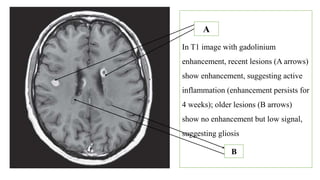

In T1 image with gadolinium

enhancement, recent lesions (A arrows)

show enhancement, suggesting active

inflammation (enhancement persists for

4 weeks); older lesions (B arrows)

show no enhancement but low signal,

suggesting gliosis

A

B